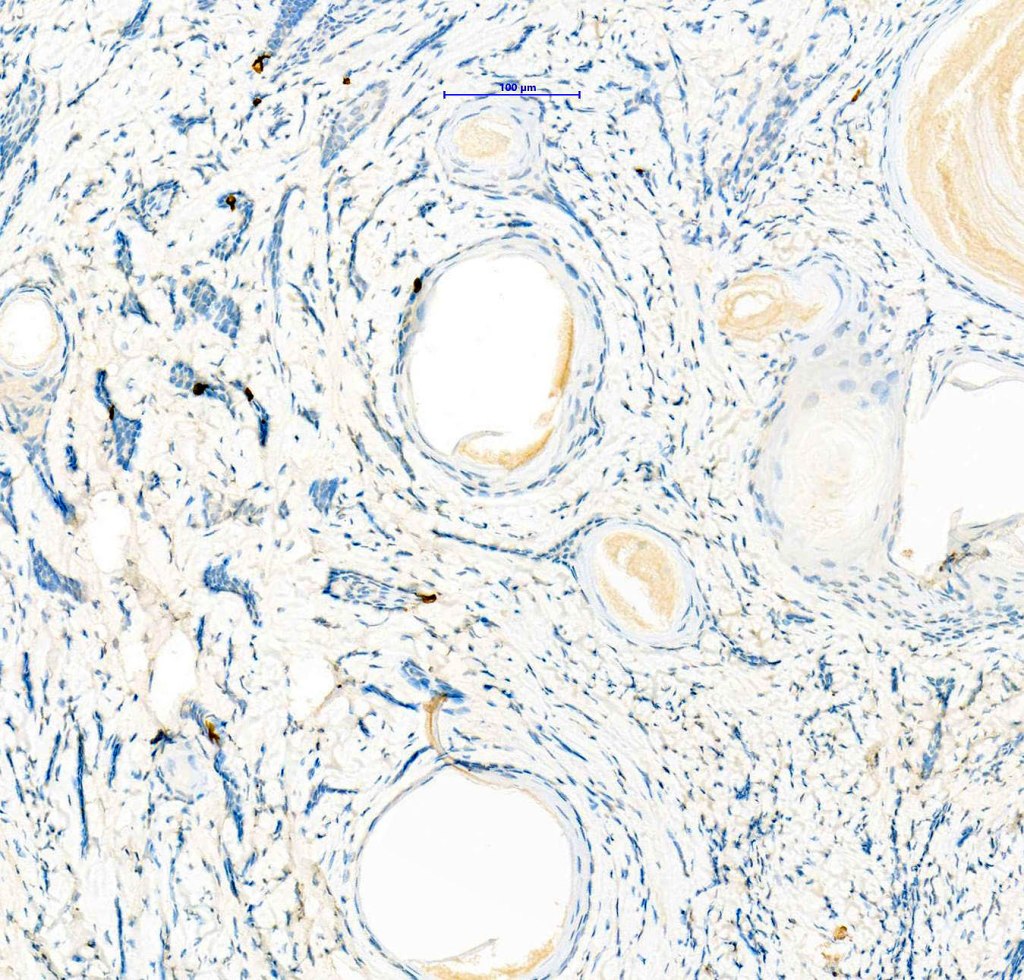

•CK20 highlights Merkel cells

•Perineural infiltration is documented but is exceptional & makes differentiation from MAC difficult

. EMA & CEA show no evidence of ductal differentiation